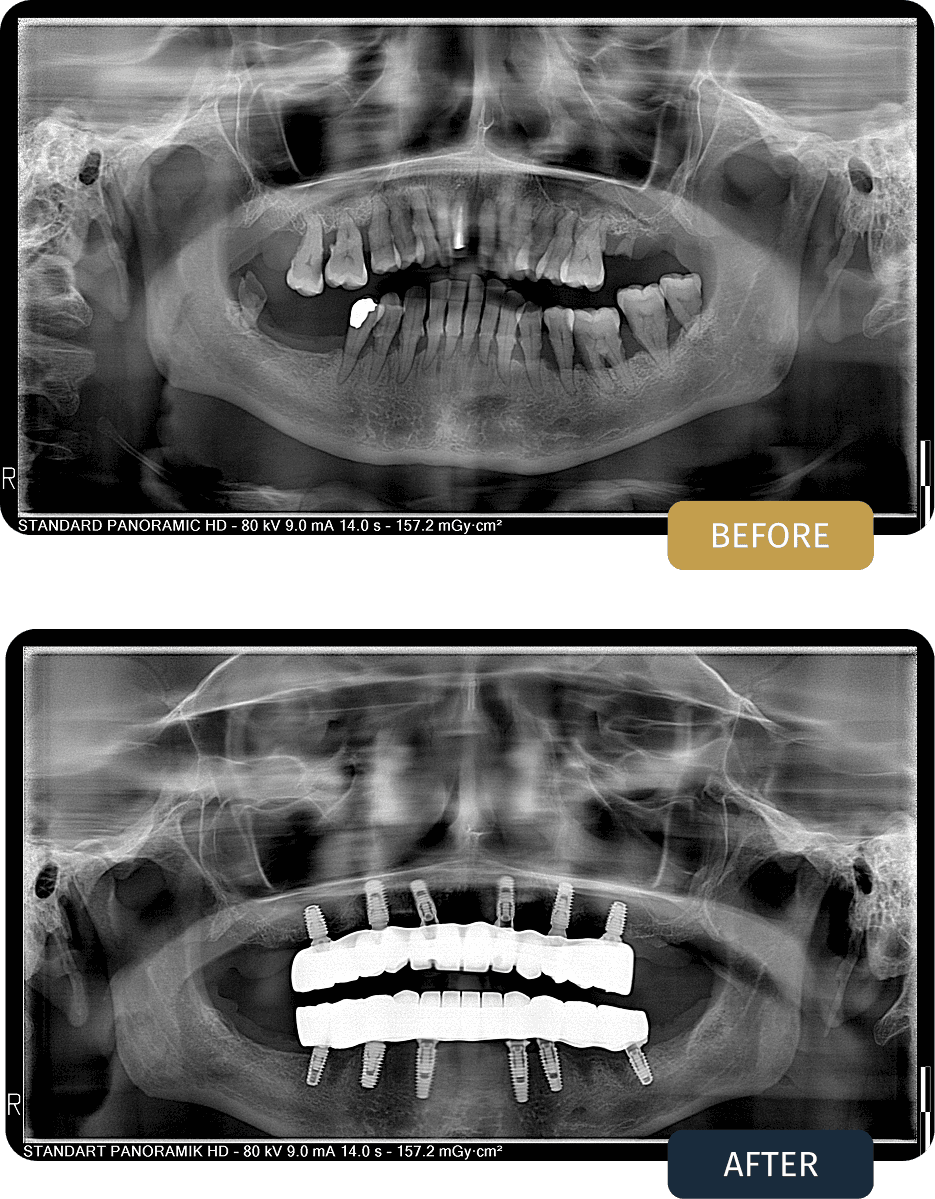

BEFORE

Lisa presented with advanced tooth loss, compromised bite stability, and progressive functional limitations affecting both jaws.

Clinical examination and panoramic imaging showed insufficient remaining dentition to support conventional restorative treatments. Bone quality and distribution indicated that a full arch implant solution was the most predictable option for long term function and stability.

AFTER

Post treatment panoramic imaging confirmed stable implant placement in both jaws with well seated titanium bars and accurately fitted full arch restorations.

The final outcome delivered a fixed, balanced bite with improved chewing efficiency, comfort, and long term dental stability.